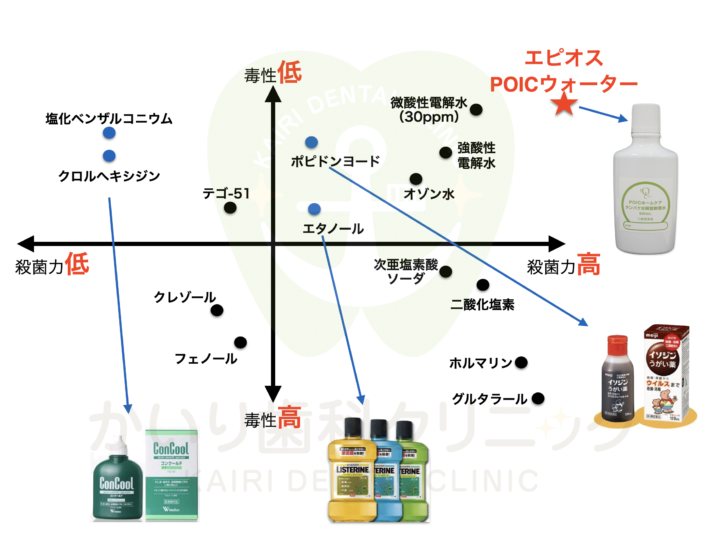

POICウォーターってなに?

2024.06.04

昨今、様々な洗口液が市場に出回っていますが、当院でおすすめする洗口液のPOICウォーターについてご紹介致します。

『POICウォーター』ってなに?

POICウォーターは純度99.9%の塩と不純物を限界まで取り除いた超純水を電気分解させた電解機能水です。

強い殺菌力がありますが消毒薬と違い人体の免疫成分と同成分のため安全性が認められている殺菌水になります(厚生労働省食品添加物認可)

どんな効果があるの?

・虫歯菌の減少

・歯周病菌の減少

・歯茎の炎症の改善

・口臭予防

市販の洗口液の違いは?

市販の洗口液はアルコール系などの様々な薬品を含みますが、POIC ウォーターは純粋な塩と水を電気分解して作られ、細菌の作るバリアを破壊することもできる安心・安全で非常に除菌効果に優れた電解機能水です。

しかし市販の洗口液は殺菌力は高くなくいが、清涼感があり長期保管が可能である一方で、POICウォーターは作ってから保存期間が短く冷蔵庫に保管が必要になります。

当院では、POICウォーターを精製する機械を導入しており、患者様からの依頼に合わせて都度精製しております。

開封前は3ヶ月 開封後は1~2ヶ月